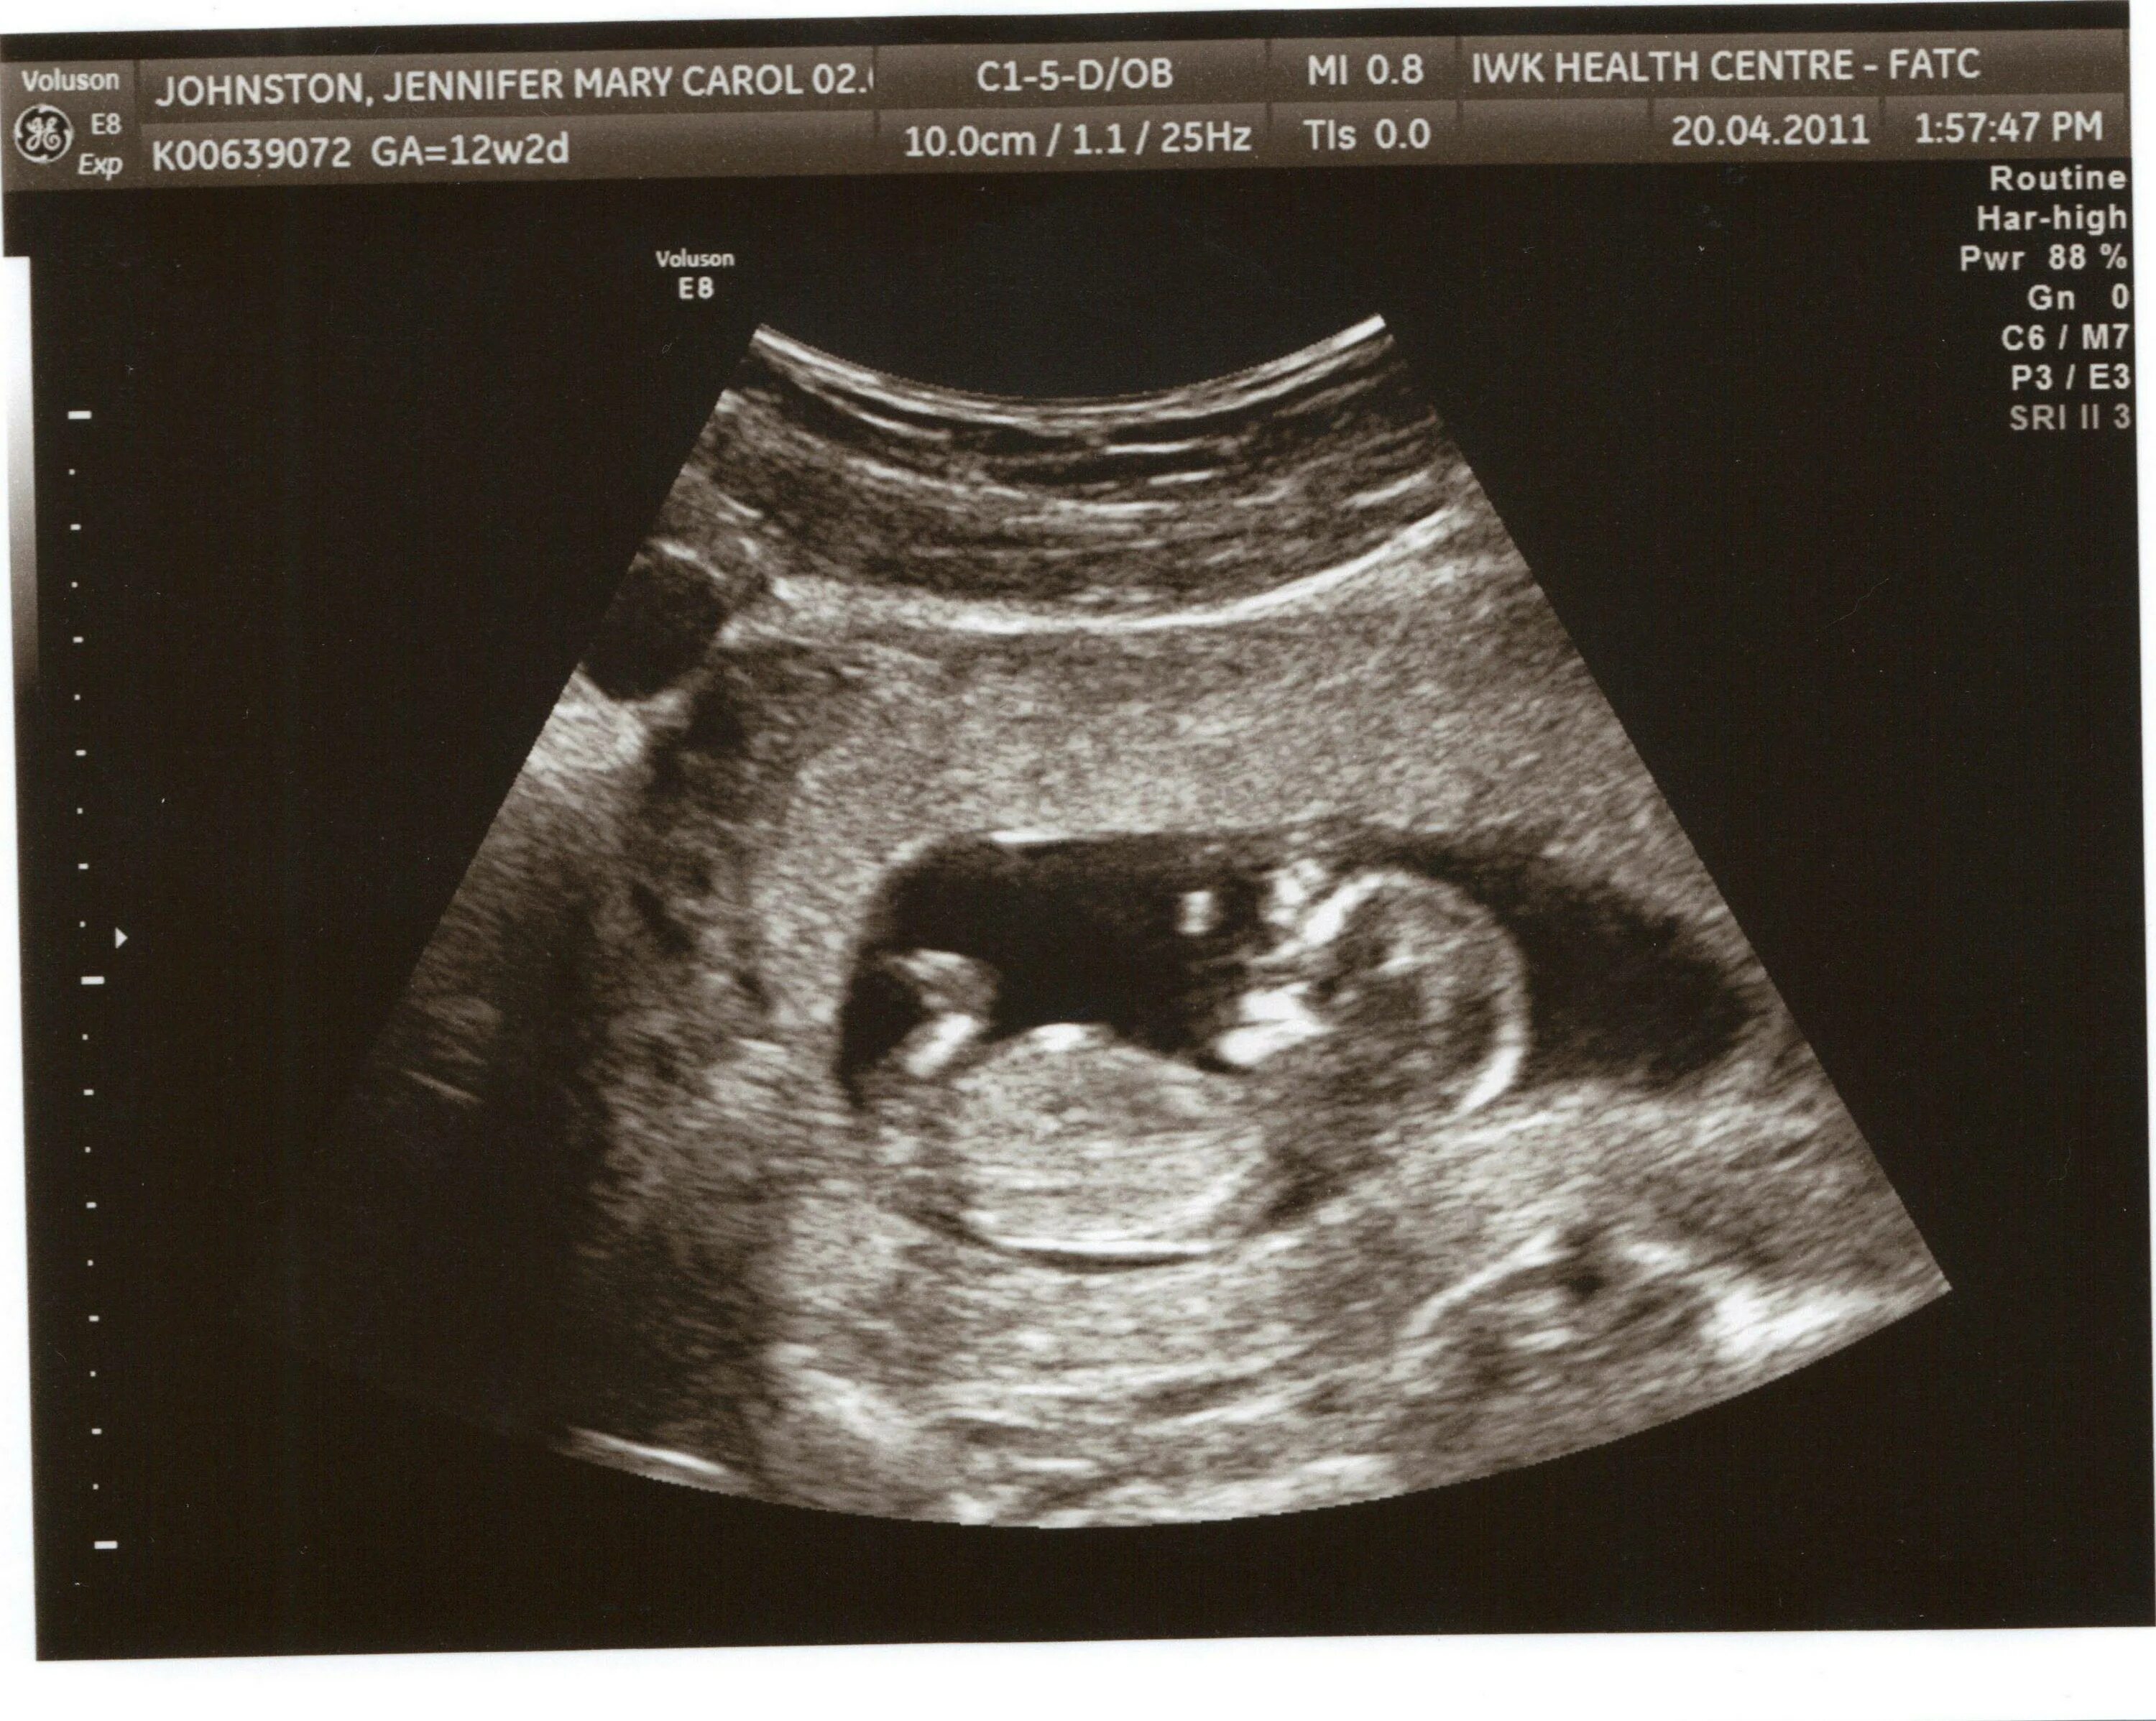

Узи 10 дней беременности